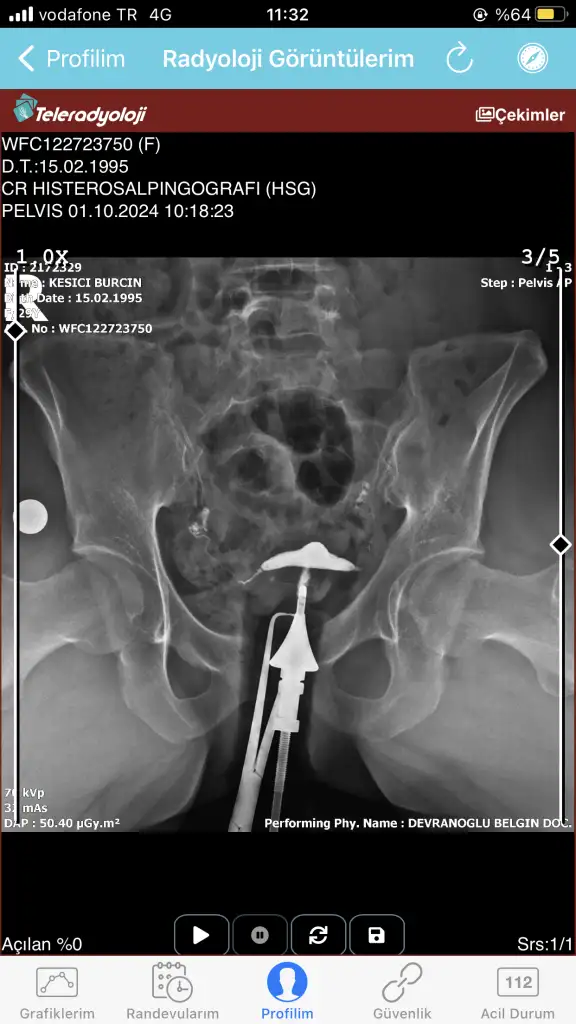

Bugün çekildim doktora gösteremedim daha anlayan yardımcı olabilir mi